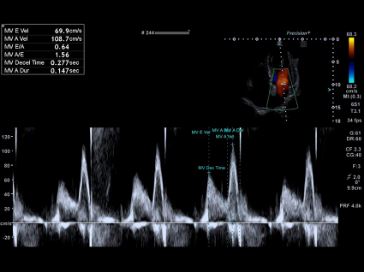

Автоматизовані інструменти вимірювання та аналізу з підтримкою штучного інтелекту можуть допомогти підвищити точність, послідовність і швидкість досліджень. За допомогою Auto GLS (Quick Strain) комплексна оцінка лівого шлуночка або іншої камери серця, включаючи фракцію викиду та глобальну поздовжню деформацію, досягається простим вибором відповідного зображення.

Автоматичне допплерівське стеження спрощує робочий процес за допомогою імпульсно-хвильових допплерівських (PWD) вимірювань.